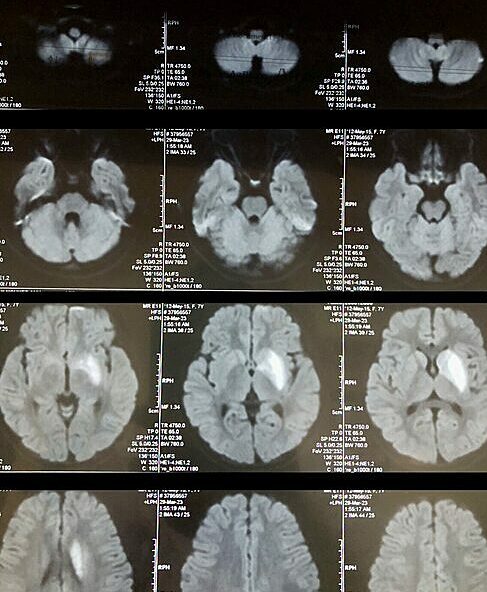

Hình ảnh chụp tình trạng nhồi máu não của bệnh nhi. Ảnh: Bệnh viện cung cấp

Theo bác sĩ Nguyễn Thành Trung, Trung tâm Đột quỵ, Bệnh viện Đa khoa Phú Thọ, ban đầu cháu được sơ cứu tại Trung tâm Y tế huyện. Sau đó chuyển Bệnh viện Nhi Trung ương với chẩn đoán nhồi máu não nhân bèo trái không rõ nguyên nhân, liệt dây thần kinh số 7 ngoại biên phải.

Sau 9 ngày điều trị tại viện Nhi Trung ương, bé được chuyển về Trung tâm Đột quỵ, Bệnh viện đa khoa tỉnh Phú Thọ, tập phục hồi chức năng. Lúc này, bé còn méo miệng, nói chưa tròn tiếng, nửa người bên phải yếu, đi lại cần sự trợ giúp, không thể tự đánh răng, rửa mặt, buộc tóc. Bé cầm nắm đồ vật nhỏ rất khó, không thể viết chữ.